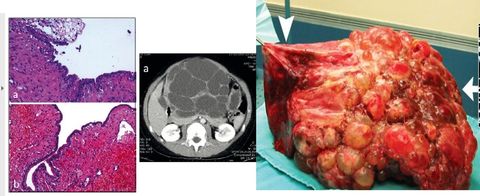

EQUINOCOCOSIS